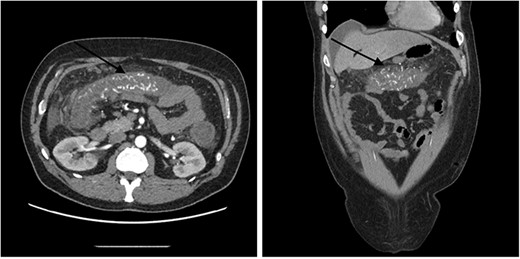

A 51-year-old male patient presented to the emergency department with 24 hours of severe abdominal pain and rectal bleeding, as well as 4 months history of non-mucous diarrhoea with stool frequency of up to 12 episodes per day. He had a background of poorly differentiated adenocarcinoma of the ascending colon (T3N0M0), which was treated with laparoscopic right hemicolectomy 1 year prior to this presentation. His follow-up colonoscopy 6 months prior to admission demonstrated evidence of diverticular disease and colitis although biopsies were normal. On admission, the patient was haemodynamically stable and physical examination did not reveal signs of peritonism. Laboratory studies demonstrated a haemoglobin drop of 4 g/dl (15.9–10.8 g/dl) but no evidence of abnormal coagulation. Stool samples were negative for infectious causes. The diagnosis of ischaemic colitis was made by contrast-enhanced computed tomography (CT) scan with CT angiography, which revealed AVMs in the territory of SMA and IMA and acute massive congestive ischaemic colitis affecting remaining colon and rectum (Figs 1 and 2).

Contrast-enhanced abdominal CT images of superior mesenteric AVM causing acute congestive ischaemic colitis affecting transverse colon.